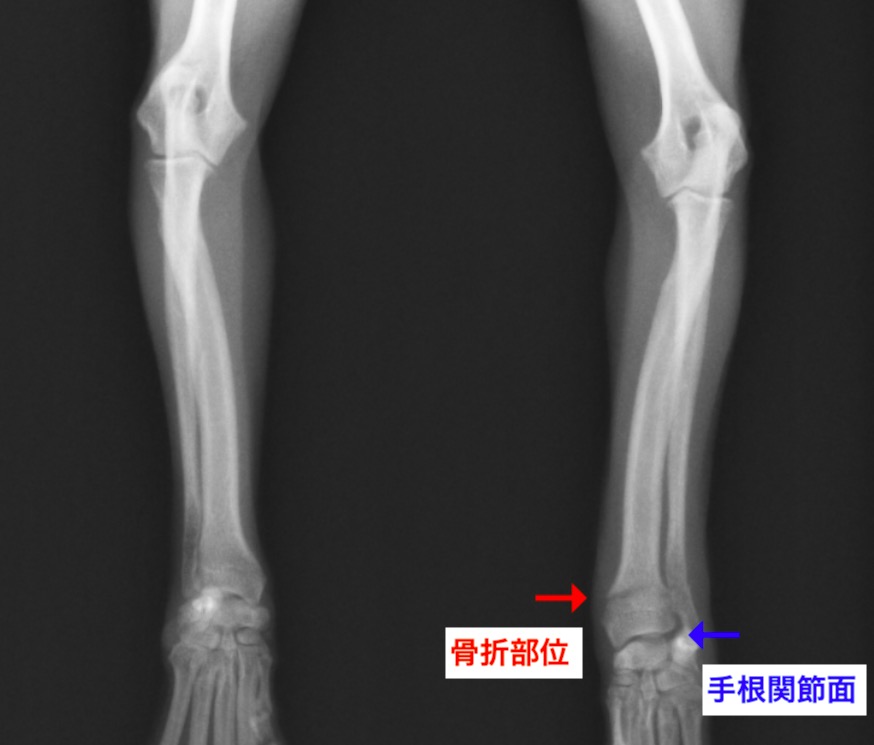

今回ご紹介する症例は橈尺骨骨折の中でも手首の関節に近い部分が折れてしまったチワワさんでした。

関節面から骨折線までは6mm程度しかありませんでした。